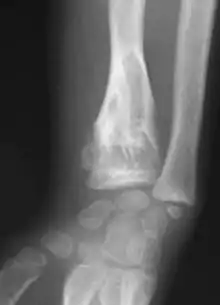

Enchondromas localized in the upper part of the humerus of the same patient